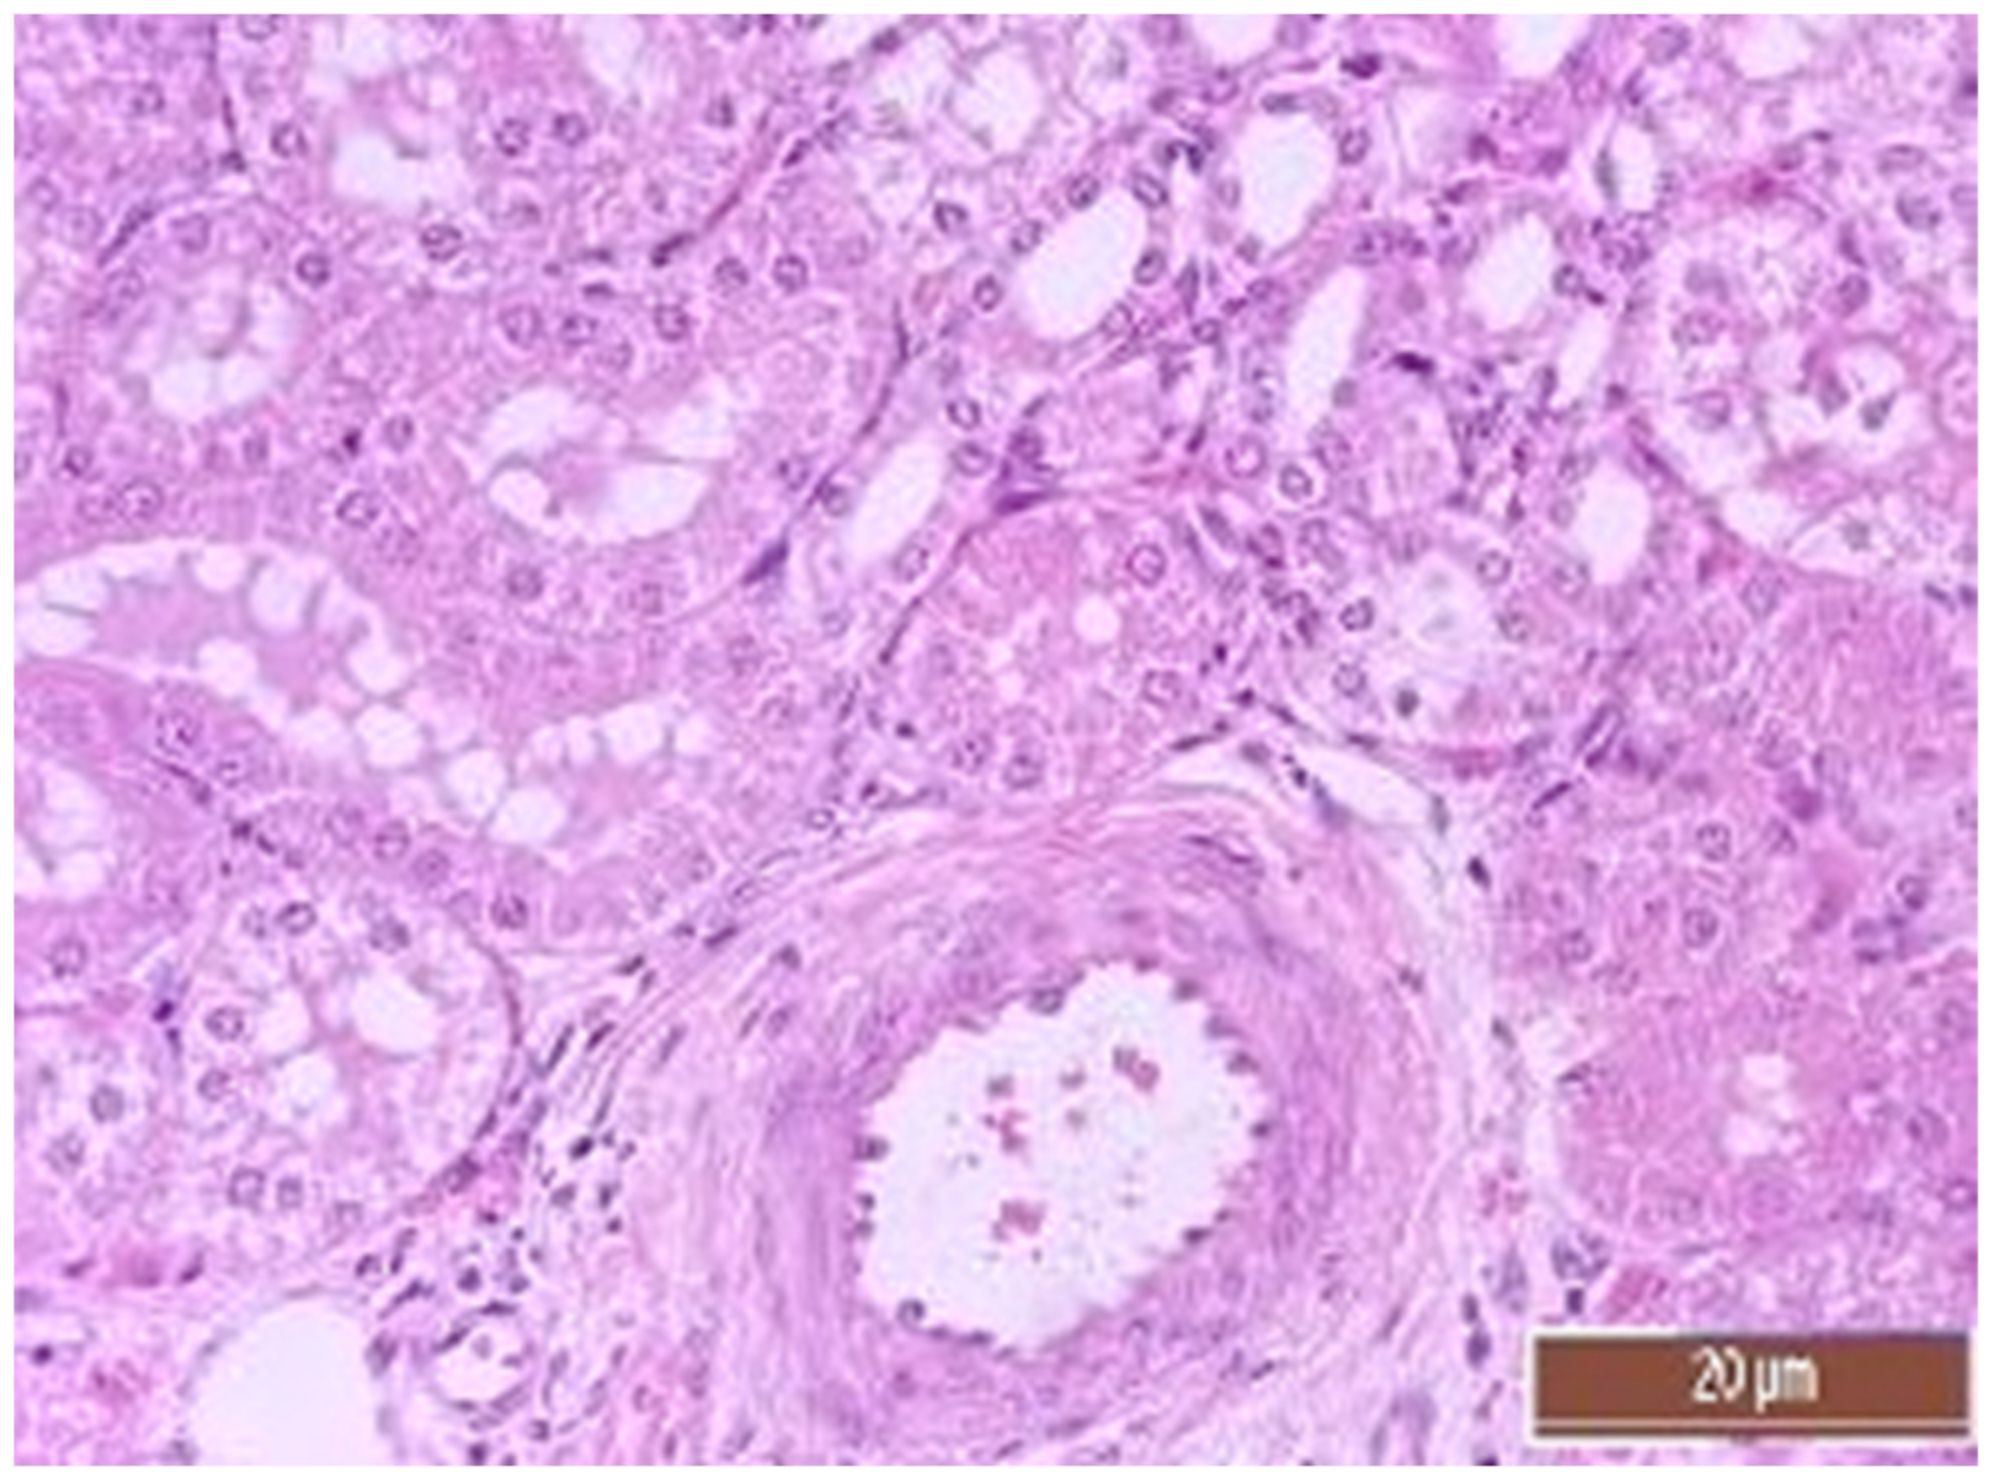

3.4. Pathology of Kidneys

| Value | Group | Value, Point | Mann–Whitney U-Test |

|---|---|---|---|

| Dystrophy of the epithelium of the tubules | CPB-contr, n = 25 | 2 (1; 3) | p = 0.49 |

| CPB-NO, n = 25 | 1 (1; 2) | ||

| Lymphoplasmocytic infiltration | CPB-contr, n = 25 | 0 (0; 1) | p = 0.37 |

| CPB-NO, n = 25 | 1 (1; 1) | ||

| Hyperemia | CPB-contr, n = 25 | 2 (2; 3) | p = 0.55 |

| CPB-NO, n = 25 | 3 (2; 3) |